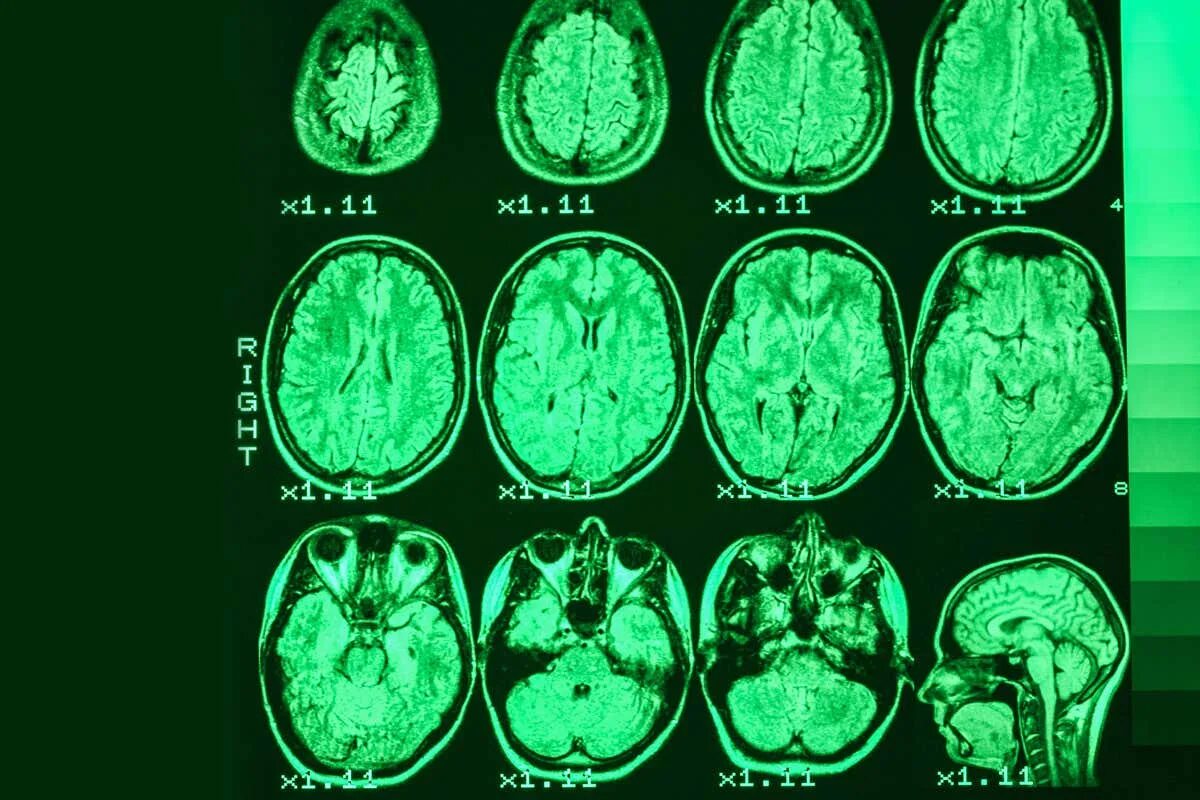

Можно заменить кт на мрт